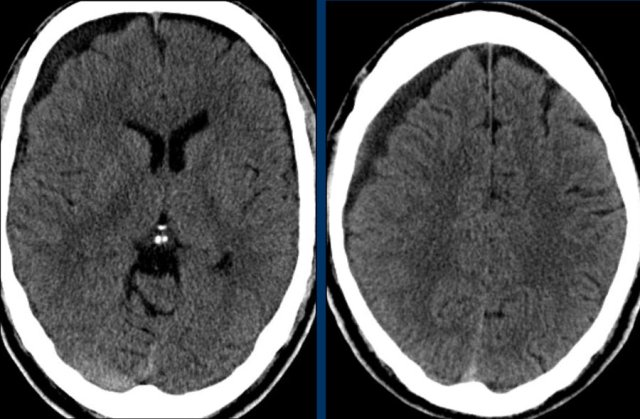

This patient has an acute subdural hematoma.

There is midline shift (left image).

The patient was operated and the hematoma was evacuated (right image).

A subdural hematoma can spread along the falx and tentorium as seen in this case.